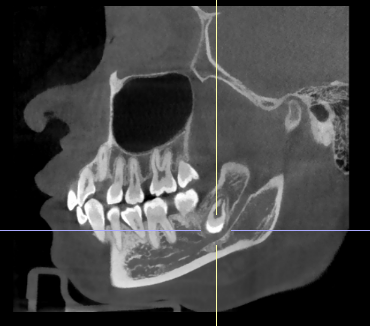

两周前,她来到烟台市口腔医院进行常规检查。在门诊检查中,王女士面部对称,口腔内左侧后牙区域的牙齿外观正常,没有疼痛或松动,牙龈也无红肿表现。然而X光片却显示左侧下颌骨存在异常肿物。进一步的高清CBCT检查揭示了隐藏危机:一颗近中倒置的智齿完全埋伏在颌骨内,其牙冠不仅紧贴前一颗牙的牙根,还紧邻着重要的下颌神经管。更严重的是,这颗“沉睡”的智齿周围已形成含牙囊肿,正在悄然侵蚀下颌骨。

医疗团队为她制定了精准的手术方案:在全麻下实施“左下颌骨病损切除术+阻生牙拔除术”。手术成功清除了囊肿并拔除了“肇事”智齿,同时尽可能保留了相邻的牙齿。术后王女士恢复顺利,因肿物紧贴神经导致的下唇麻木,也会随着时间逐渐恢复。